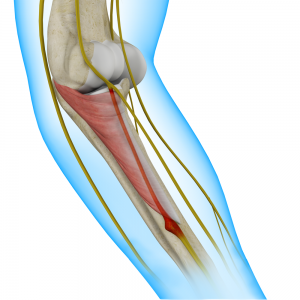

The triceps or triceps brachii is a crucial muscle of the upper arm (humerus). It runs along the upper arm bone between the shoulder and elbow.

Cubital Tunnel Syndrome (Ulnar Nerve Entrapment)

When the ulnar nerve is compressed or entrapped, the nerve can tear and become inflamed, leading to cubital tunnel syndrome.